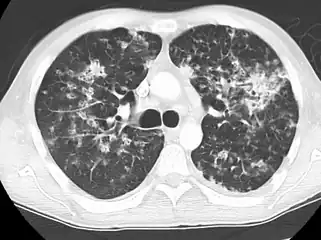

High-resolution CT image showing ground-glass opacities in the periphery of both lungs in a patient with COVID-19 (red arrows). The adjacent normal lung tissue with lower attenuation appears as darker areas.

Ground-glass opacity is among the most common imaging findings in patients with confirmed COVID-19.[16][17] One systematic review found that among patients with COVID-19 and abnormal lung findings on CT, greater than 80% had GGOs, with greater than 50% having mixed GGOs and consolidation.[16] GGOs with mixed consolidation has most often been found in elderly populations.[18] Several studies have described a pattern among initial, intermediate, and hospital discharge imaging findings in the disease course of COVID-19. Most commonly, initial CT imaging reveals bilateral GGOs at the periphery of the lungs. During initial stages, this is most often found in the lower lobes, although involvement of the upper lobes and right middle lobe has also been reported early in the disease course.[16][18] This is in contrast to the two similar coronaviruses, SARS and MERS, which more commonly involve only one lung on initial imaging.[19][20] As the COVID-19 infection progresses, GGOs typically become more diffuse and often progress to consolidation.[11][18] This is sometimes accompanied by the development of a crazy paving pattern and interlobular septal thickening.[18] In many cases the most severe pulmonary CT abnormalities occurred within 2 weeks after symptoms began.[17] At this point, many individuals begin showing resolution of consolidation and GGOs as symptoms improve. However, some patients have worsening symptoms and imaging findings, with further increase in septal thickening, GGOs, and consolidation. These patients may develop lung "white-out" with progression to acute respiratory distress syndrome (ARDS) requiring treatment escalation.[17][21]